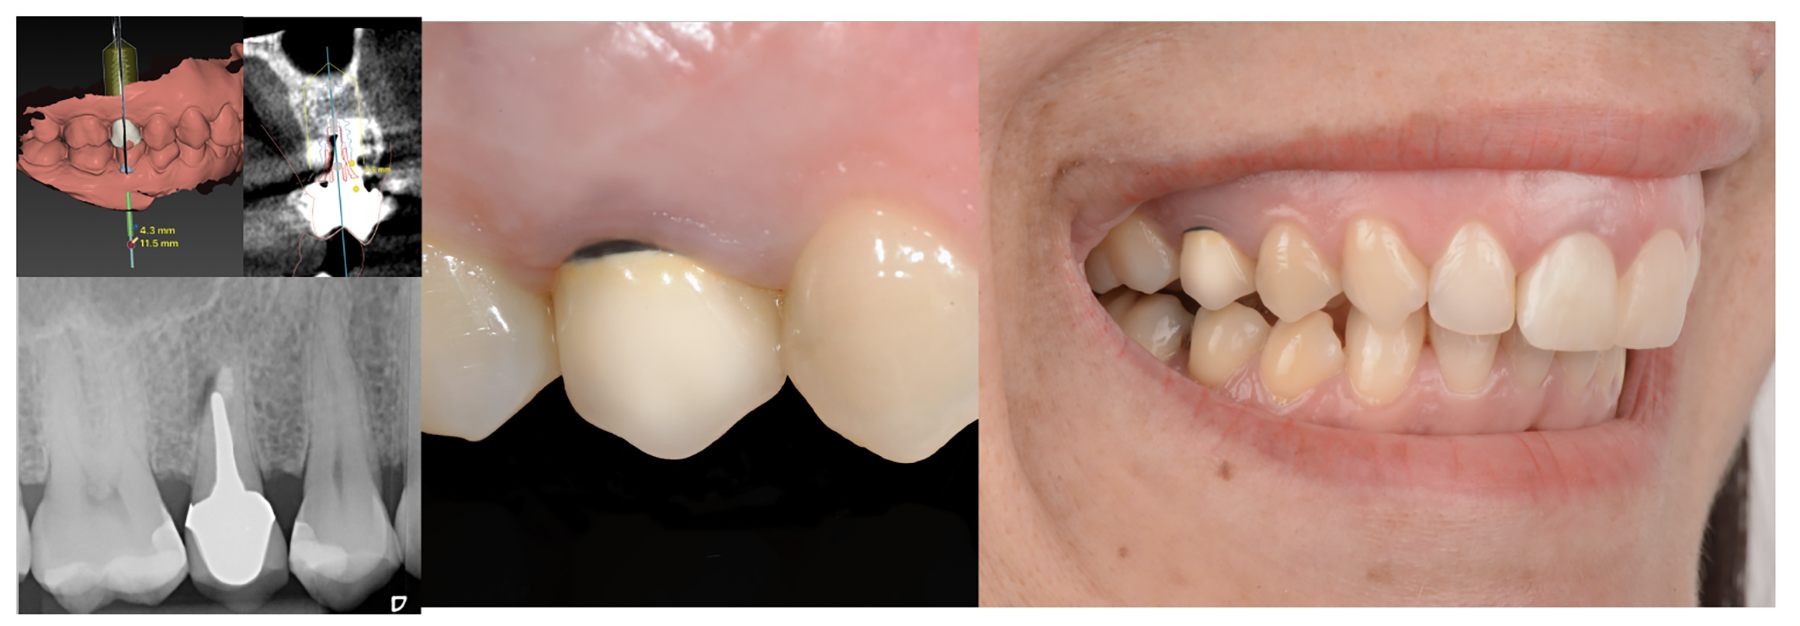

One final important factor to consider in the creation of the emergence profile is the clinical approach used for the placement of the implants, particularly with regard to planning the vertical position of the implants in the corono-apical direction, and for implementing the abutment placement protocol. The achievement of proper implant restorative contours is highly dependent upon the 3D spatial location of the implants.33,34

As discussed earlier, the biological width requires a minimal dimension to accommodate soft tissue healing. If the biological width is adequate, the crestal thickness of soft tissues should include the peri-implant soft tissue barrier or defense zone protecting the bone.8,13 A vertical distance of at least 3 to 3.5 mm (ie, a 2-mm-high epithelial apparatus and a 1.5-mm-high supracrestal connective tissue13,14,25,27,30,31,35) from the implant/abutment interface to the free mucosal margin should be considered to accommodate the biological width in the soft tissue thickness, avoid

crestal bone loss, and provide minimal vertical space to design the emergence profile (Figure 5 and Figure 6). This height should allow an ideal emergence profile morphology, avoiding excessively angled and steep horizontal components that could compromise oral hygiene maintenance. To achieve a gradual emergence profile in esthetic areas, the vertical distance may be increased up to 4.5 to 5.0 mm (Figure 2), particularly when the implants are placed slightly palatally. If the soft tissue thickness is not adequate, it will be necessary to increase it surgically (in particular in the frontal areas) or modify the vertical position of the fixture. Many studies have reported that adapting the vertical position of implants in relation to soft tissue thickness can prevent early implant surface exposure 8,10,13; however, this approach should be taken only when using implant systems with a stable conical connection and platform switching (Figure 1).6-10,29,33,34

Finally, once the proper 3D position of the implants has been identified, the abutment placement protocol to be used should be evaluated. The "one abutment/one time" approach4,6,8,17 allows soft tissues to adhere firmly onto the surface of titanium abutments, thereby improving soft tissue response and bone stability (Figure 4 and Figure 7 through Figure 14 ). This approach avoids multiple connections and disconnections at the bone interface and favors undisturbed bone and soft tissue healing.4-7